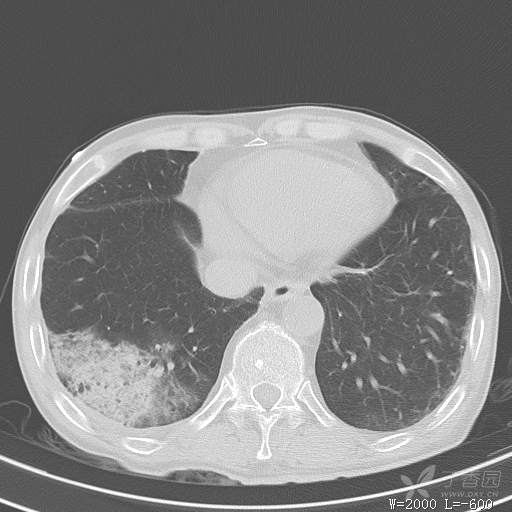

简要病史:主因发热伴腰背部疼痛2小时于2018-06-27,09:30 入院。患者无高血压,冠心病、糖尿病病史,无慢性咳喘史,不吸烟。否认食物药物过敏史。患者于入院前2小时出现发热,体温37.5℃,无咳嗽,咳痰,伴右侧腰背部疼痛,伴呕吐2次,呕吐物为黄绿色胆汁,大便2次,为稀便,无咯血,无胸闷、憋气,无鼻塞、流涕,无尿频、尿急、尿痛,就诊于我院,我院急诊查:上腹部CT:右肾结石,右下肺感染性疾病可考虑,血常规WBC13.54*109/L,GR%45.8%,急诊以“发热待查:肺感染?”收入院。

辅助检查:上腹部CT:右肾结石,右下肺感染性疾病可考虑,血常规:WBC13.54*109/L,GR%45.8%,。心肌酶示:谷草转氨酶12U/L,乳酸脱氢酶328U/L,肌酸激酶20U/L,肌酸激酶同工酶7U/L,α-羟丁酸脱氢酶277U/L,查凝血常规示:凝血酶原时间12.5秒,国际标准化比值1.07,活化部分凝血酶原时间32.6秒,纤维蛋白原浓度1.77g/L,凝血酶时间15.6秒。

临床诊断:1.腰背部疼痛原因待查:1.肺炎?2.泌尿系结石?。

治疗经过:抗感染及止痛对症处理。治疗效果不好,患者腰痛是由什么引起的?